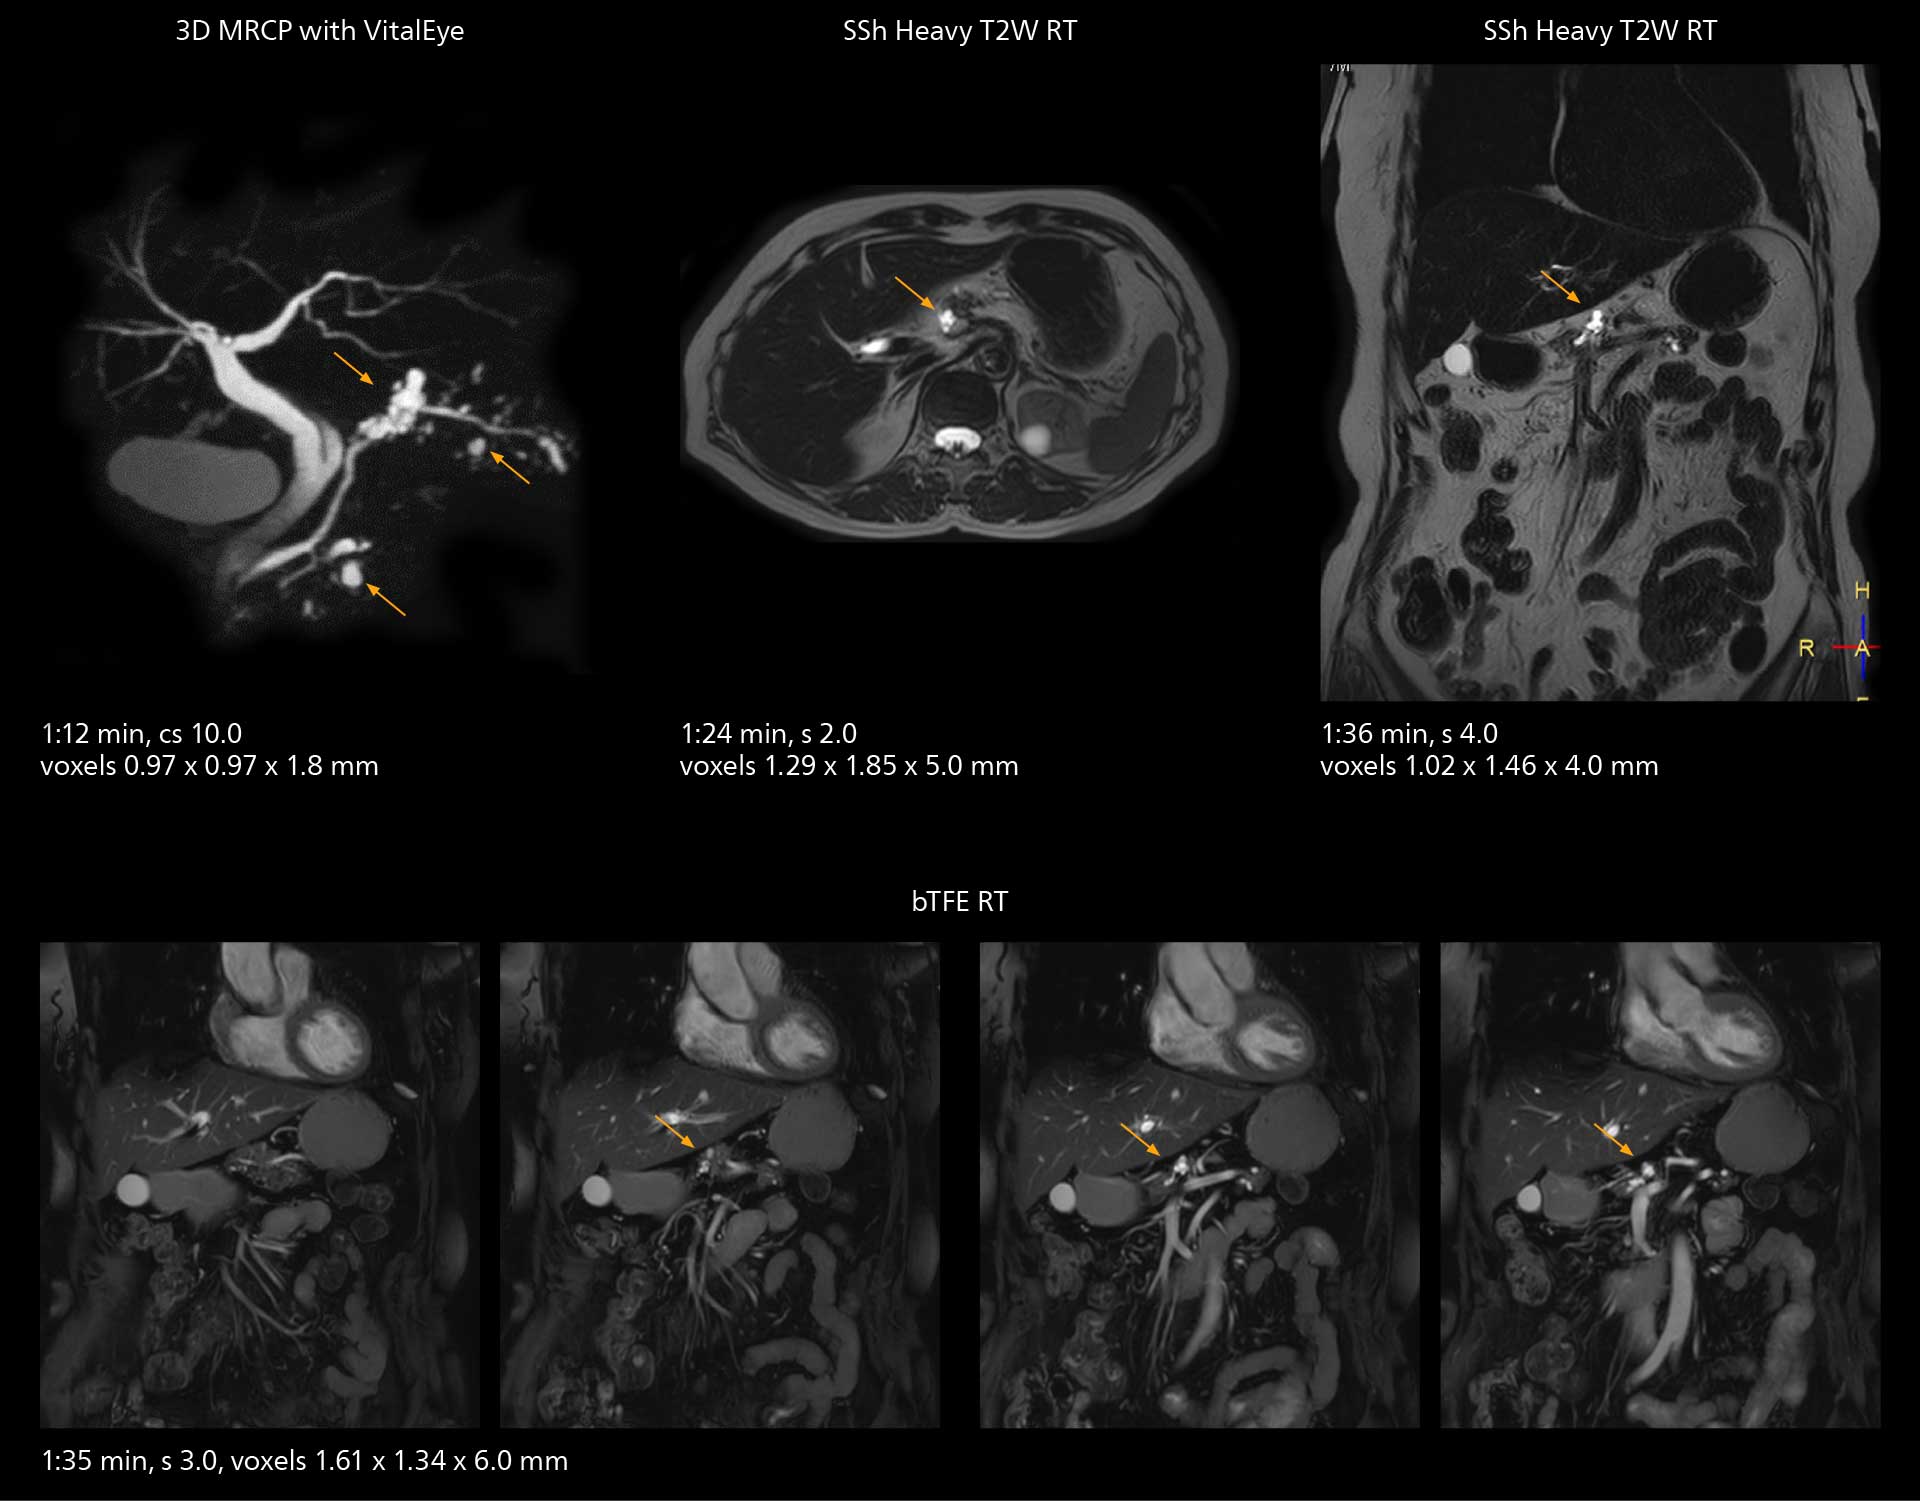

Workflow innovations streamline studies

SmartPath to Elition X comes with Smart Workflow technologies that support technologists and can save them time. VitalEye for touchless patient sensing is one example. “The implementation of VitalEye respiratory synchronization has had a significant impact,” says MR technologist Yoshihiro Otsu, Chief of the Radiological Department. “It not only improves workflow, but it also has increased the quality of examinations. Particularly for the large number of MRCP examinations performed in this hospital, VitalEye has increased the possibility to obtain sharp images with less blurring. Clinicians here really appreciate this improvement in MRCP image quality.” The VitalScreen on the scanner has helped reduce the risk of patient misidentification. “It allows patient information to be viewed in the magnet room when standing next to the patient,” he says. “And the automated patient centering in the magnet is very useful as well.” Apart from reducing stress for technologists, Smart Workflow helps improve respiratory synchronization and reduce examination stress for the patient.

VitalEye has increased the possibility of obtaining sharp images with less blurring. Clinicians here really appreciate this improvement in MRCP image quality.”

Yoshihiro Otsu

MRCP

With SmartPath to Elition X, the MRCP examinations at Sannodai Hospital benefit from VitalEye: respiratory synchronization is possible without respiratory belt positioning and image quality is excellent.

MRCP

With SmartPath to Elition X, the MRCP examinations at Sannodai Hospital benefit from VitalEye: respiratory synchronization is possible without respiratory belt positioning and image quality is excellent.